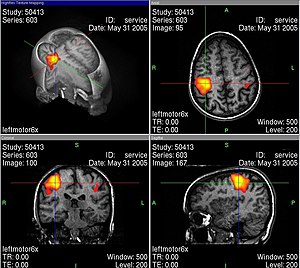

L’usage de l’imagerie cérébrale dans des programmes de recherche en neuropsychologie nécessite de bien maîtriser tous les artefacts et biais statistiques possibles, par exemple lors de l’IRMf en faisant des moyennes spatiales, temporelles et interindividuelles. La base de cet examen est de déterminer des corrélations entre certaines tâches mentales (langage, attention, mémoire…) et des activations spécifiques de zones du cerveau[33].

Les activités électriques du cerveau conduisent à des variations de tension électrique à la surface de la tête, que l'on peut enregistrer avec des appareils convenables. Les neurosciences cognitives actuelles reposent très largement sur le procédé d'imagerie par résonance magnétique fonctionnelle (IRMf). En même temps, ce genre de méthode soulève déjà une série de questions éthiques. Au moyen de l'IRMf, l'activité dans le cerveau peut être mesurée avec une bonne définition spatiale et temporelle. Cette technique conduit à des problèmes éthiques en particulier quand on trouve au moins grossièrement des corrélations entre l'activité neuronale et l'état conscient du sujet. Comment se comporter quand on sait par des méthodes neurologiques, et non par ce qu'elle en dit, qu'une personne pense à quelque chose ou le sent ?

Les images d'IRMf bien connues (voir par exemple ci-contre) sont toujours interprétées selon des modèles qui en permettent la lisibilité. Pendant une tâche cognitive, le cerveau est constamment actif dans un grand volume, et il faut trier pour obtenir des images significatives, dépourvues de toutes les activités apparemment secondaires. Ce genre de tri se fait avec une méthode de soustraction : par exemple si l'on s'intéresse à une tâche cognitive K, alors on mesure l'activité du cerveau dans une situation S1 dans laquelle K est accomplie. Ensuite, on mesure l’activité dans une situation de contrôle S2 qui ressemble à S1, mais qui n'a a priori rien à voir avec la tâche K. Finalement, on soustrait les activités mesurées dans S2 de celles mesurées dans S1, pour voir les activités corrélées avec la tâche K de façon spécifique. Illes souligne qu'il faut toujours garder en tête ces aspects interprétatifs, ce qui peut facilement passer inaperçu devant un tribunal, parce que les juristes n'ont probablement aucune compétence en neurologie.